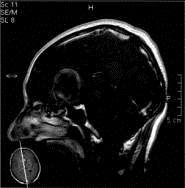

问题 病历摘要:??患者男性,56岁,因右侧视力下降伴视野缺损2个月来院就诊,诉头痛,无明显头晕,无视物重影,无恶心呕吐,无肢体抽搐,无肢体乏力,胃纳佳,大小便正常,既往史无特殊,入院检查:神志清楚,言语清楚,体毛分布正常,左侧视力4.6,右侧视力4.0,粗侧右颞侧视野缺损,左侧正常,颈软,四肢肌张力正常,肌力正常,病理征(-)。 该患者入院应行下列那些检查?

选项 A.头部CT B.头部MRI C.性激素检查 D.视觉诱发电位 E.视野检查 F.癌胚抗原检查

答案 ABCDE